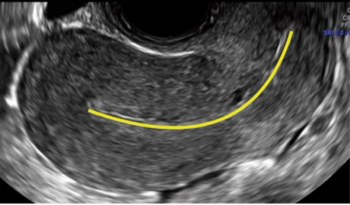

An oral selective estrogen receptor modulator approved for treatment of mild to moderate dyspareunia in menopausal women reduced signs and symptoms of atrophy in the vulva, vestibule, urethral meatus and vagina region, according to results of a prospective open-label pilot study